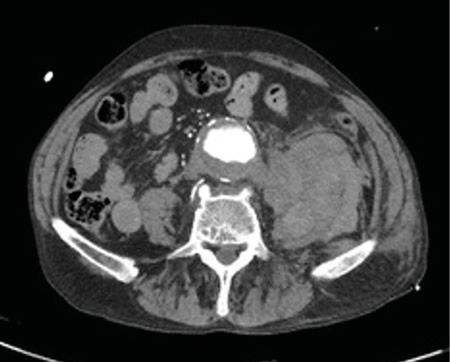

No es solo dolor lumbar: manifestación atípica del aneurisma de aorta

Not just low back pain: atypical manifestation of aortic aneurysm

La rotura de aneurisma de aorta supone el síntoma principal en hasta un 25 % de los casos de la patología de aneurisma de aorta, que constituye una entidad potencialmente mortal. También puede aparecer con menor prevalencia como lumbalgia, coxalgia e, incluso, gonalgia, no comentándolo como dolor vertebral o neuropático, sino como irritación a nivel de psoas ilíaco como primera sintomatología.

Se estima que solo en un 50 % de los casos aparece la triada clásica del aneurisma, por lo que es necesario tener un alto nivel de alerta para sospecharlo, ya que la hipovolemia puede estar contenida por un hematoma peritoneal.

Figura 1